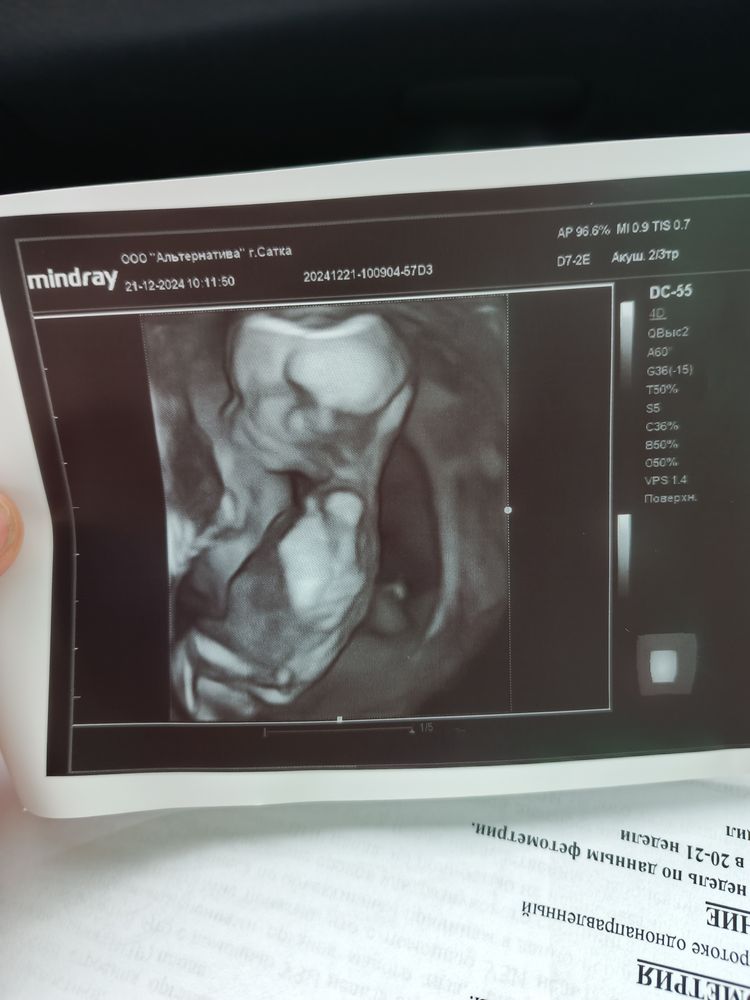

Марина в Клуб беременных 10 месяцев Пол ??? Пол малыша Здравствуйте. Виден пол ? 🤣 фото в комментах Посмотрите еще 20 записей на эту тему Лучший ответ Юленька Это какое место сфоткано 🤣 Вам врач на таком сроке не сказал? 02.02.2025 Ответить Юленька Юленька, по второму фото хоть понятно что где) но там голова и животик, половые органы ниже, не в кадре( 02.02.2025 Ответить Марина Юленька, прикрепила ниже , может что видно 🤣 02.02.2025 Ответить Марина Комментарий удален 02.02.2025 Ответить Марина Юленька, сказала , но я сомневаюсь так как нечего на снимках не вижу 🤣сказали будет мальчик 02.02.2025 Ответить Отменить Ответить Марина 02.02.2025 Ответить Мария Нужно фото вбок где будет видно половой бугорок, по профилю лица пол не определить 02.02.2025 Ответить Марина Мария, прикрепила ниже 02.02.2025 Ответить Мария Марина, мальчик 02.02.2025 Ответить Кира Виден только ребенок 02.02.2025 Ответить Марина Кира, прикрепила ниже 02.02.2025 Ответить Victoria Фото нет 02.02.2025 Ответить Марина Victoria, 02.02.2025 Ответить Марина Victoria, 02.02.2025 Ответить Victoria Марина, тут точно не видно. 02.02.2025 Ответить Марина Victoria, блин фотки не могу прикрепить , у всех такие проблемы , типа не загружает 02.02.2025 Ответить Марина Victoria, а ниже 02.02.2025 Ответить Gulnar Mamedova Марина, на мальчика похож 03.02.2025 Ответить Пол по крови. Вероятность ошибки😏 У нас будет ЗДОРОВЫЙ сынок🙏🏼🙏🏼🙏🏼🙏🏼 Чаты Беременных Выберите чат: Январята-2026 Февралята-2026 Мартята-2026 Апрелята-2026 Майчата-2026 Июнята-2026 Июлята-2026 Августята-2026